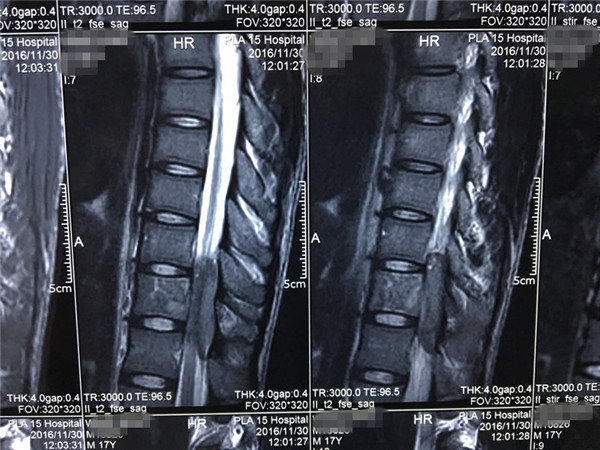

术前 MRI